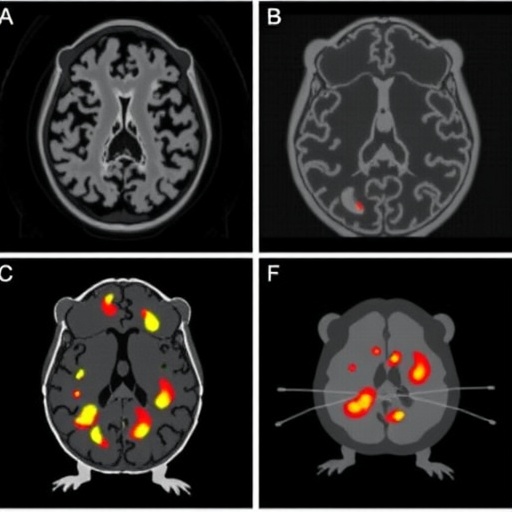

The study investigates the efficacy of various ^18F-labeled radiopharmaceuticals, which are critical for Positron Emission Tomography (PET), an imaging modality that has transformed our understanding of neurological diseases. PET imaging relies on the principles of detecting gamma rays emitted from positron decay of radioactive isotopes that are bound to specific molecules. In Alzheimer’s research, these radiopharmaceuticals can bind to amyloid plaques, allowing for precise imaging and assessment of disease progression in vivo.

What sets this research apart is the comparative nature of the analysis, which systematically evaluates the performance of multiple PET tracers within a controlled mouse model. This is particularly significant as the choice of radiopharmaceutical can greatly influence the sensitivity and specificity of imaging the characteristic pathophysiological features of Alzheimer’s. By examining different compounds, the study provides valuable insights into which radiopharmaceuticals might yield the most informative imaging results, guiding future research and clinical applications.

In bifurcating the data among various parameters, including resolution, brightness, and binding affinity, the study meticulously cataloged the advantages and disadvantages of each radiopharmaceutical. This granularity in analysis facilitates a transparent comparison and aids in decision-making for both clinical and research settings. It emphasizes the necessity for a careful selection process when determining which radiopharmaceuticals offer the most significant benefit in diagnosing Alzheimer’s disease.